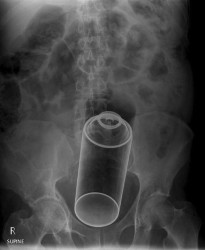

Врачи достали из прямой кишки 24-летнего француза 20-сантиметровый артиллерийский снаряд времён Первой мировой войны.

Пациенту была проведена экстренная операция, потребовавшая проведения деликатной процедуры. «Во время извлечения хирург обнаружил, что это снаряд времен Первой мировой войны, приблизительно 16 сантиметров в длину и 4 см в ширину», — сообщили Le Figaro несколько источников в полиции.

После операции больницу оцепили полицейские, была вызвана группа разминирования, но в итоге выяснилось, что «датированный 1918 годом снаряд не представлял угрозы взрыва».